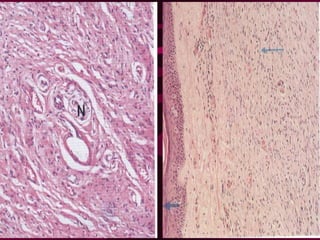

Neurofibroma: Slow growing, Benign, Well circumscribe  Not encapsulated. Lesions may be multiple & solitary  Histology:  Mixed population of  Schwann cells  Fibroblasts  Histology Spindle shaped cells with ill defined cell margins. Nuclei are ovoid or elongated but uniform. Cells dispersed in a connective tissue matrix which has collagen and fibroblasts. Myxomatous changes and nerve fibrous can be seen in the matrix.

Schwannoma(Neurilemmoma);   Cranial/spinal/peripheral nerves can de affected.  Encapsulated and appears to arise focally on the nerve trunk. So nerve stretched over the tumour. Microscopically tumour composed of elongated cells disposal in one of these two patterns.  Antoni type A - Arranged in an organised impact  manner. Palisading  of nuclei, and pink area between two palisadings (Varocay Body) Antoni type B-  cells are lossely arranged and scattered in the matrix.